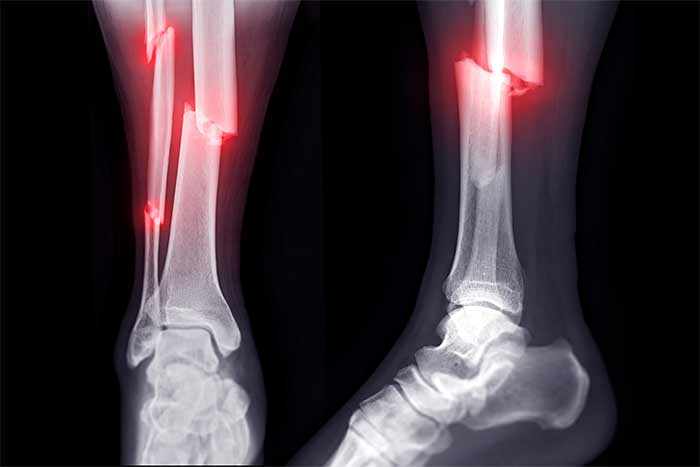

شکستگی استخوان چیه و چرا باید حواسمون بهش باشه؟

بیا ساده شروع کنیم. وقتی استخونت میشکنه، بدن تو مثل یه کارخونهی فوق پیشرفته شروع میکنه به تعمیر خودش. اول یه التهاب کوچولو اطراف محل شکستگی ایجاد میشه، بعد سلولهای خاص میان و یه بافت نرم (مثل یه چسب موقت) درست میکنن. کمکم این بافت نرم سفت میشه و به استخون جدید تبدیل میشه. اما این پروسه مثل پختن یه کیک خوشمزه زمانبره و نیاز به مواد اولیهی درست داره.

حالا اگه مواد اولیهی نامناسب (مثل غذاهای مضر) به بدن بدی یا کارخونه رو با عادتهای بد بههم بریزی، جوشخوردن استخون کند میشه یا حتی بدتر، ممکنه درست جوش نخوره! برای همین، تغذیه تو این دوره مثل یه سوپرمن عمل میکنه و میتونه سرعت و کیفیت ترمیم رو حسابی بالا ببره.